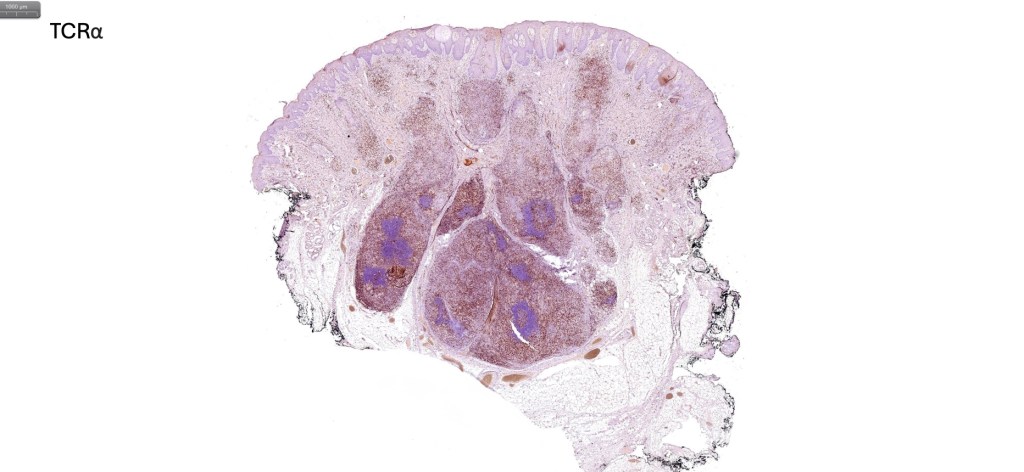

Histological features

•Follicular infiltration by atypical lymphocytes & Sézary cells